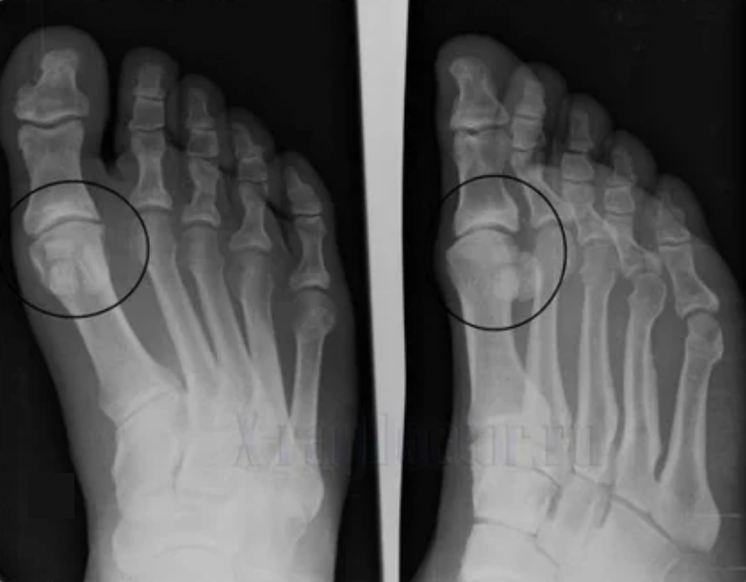

Per fare una diagnosi, i reumatologi esaminano i sintomi del paziente e prescrivono un esame di raggi X. Il più delle volte, la radiografia viene utilizzata in 2 proiezioni. Il medico esamina la presenza di disturbi distrofici nella cartilagine ialina e nelle articolazioni ossee. Quando il divario articolare viene ridotto, le ossa vengono deformate o appiattite, ci sono formazioni cistiche sulla superficie della cartilagine, gli osteofiti sono evidenti segni di osteoartrite. Durante l'ispezione, l'artrosi mostra l'instabilità dell'articolazione: l'asse degli arti e la sublussazione è disturbato.

Spesso un'immagine a raggi X non è in grado di fornire informazioni complete sulla condizione del giunto. La tomografia al computer è prescritta per uno studio più approfondito ed è efficace esaminare le ossa. La risonanza magnetica è usata più spesso per esaminare i tessuti molli.